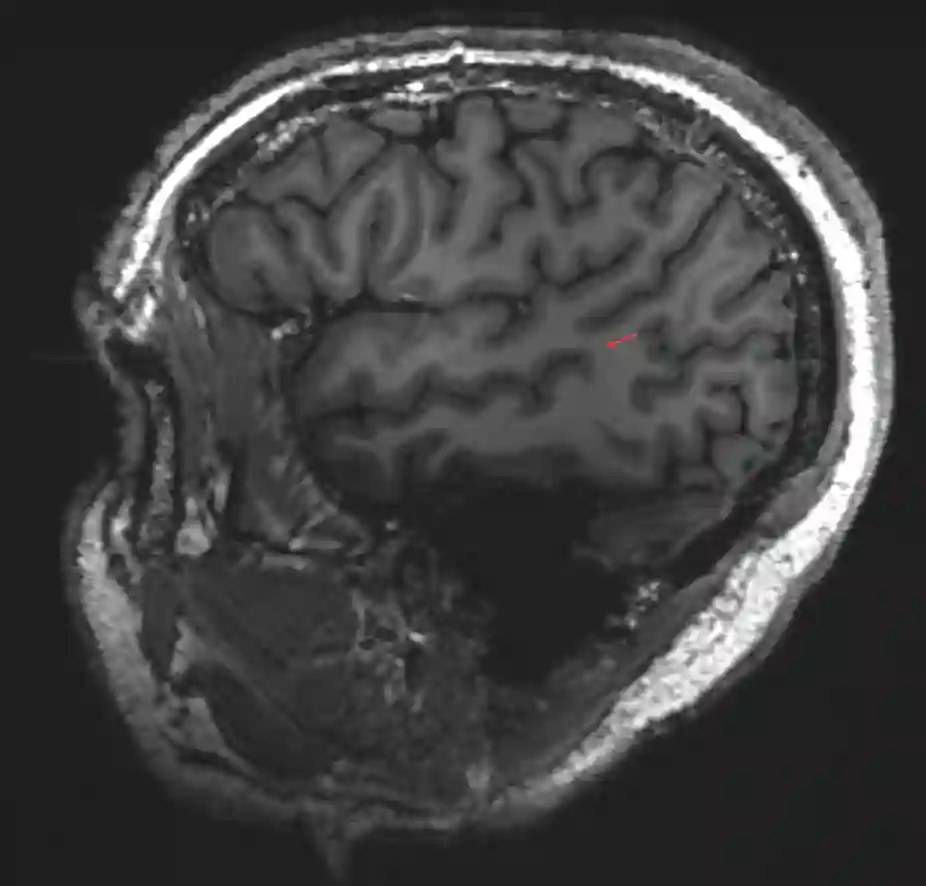

Gyrus angularis im MRI

Darstellung des Gyrus angularis (roter Pfeil) in einer sagittalen MRI Sequenz in einem 7 Tesla MRI.